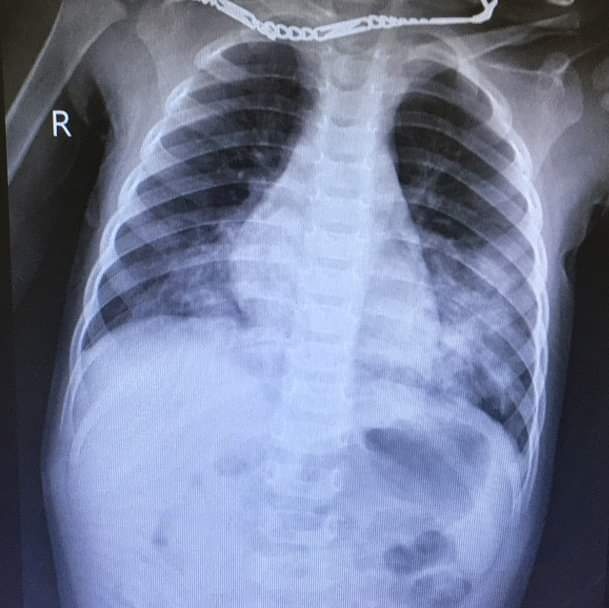

Các bác sĩ cho biết bệnh nhi nhập viện trong tình trạng quấy khóc, ho, thở nhanh, nôn ra máu. Sau khi tiến hành các xét nghiệm cần thiết, bé được chẩn đoán viêm phổi, xuất huyết tiêu hóa trên nghi ngộ độc chất tẩy trắng giày dép.

Sau khi tiến hành các xét nghiệm cần thiết, bé được chẩn đoán viêm phổi, xuất huyết tiêu hóa trên. Ảnh: BSCC.